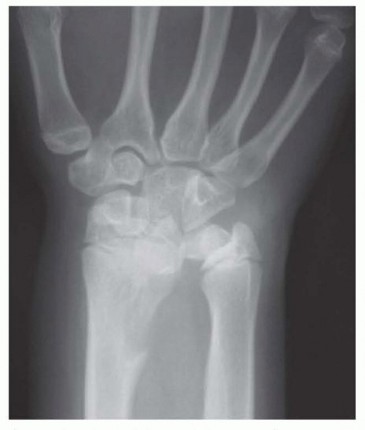

FIG 2 • Radiograph of Madelung deformity showing congenital ulnar positive variance. P.1047Analysis of whether the pain was caused by an acute injury or brought on by repetitive motion activitiesA distal radius or radial head fracture can lead to ulnocarpal impaction, as can a chronic distal radius physeal injury (ie, the gymnast’s wrist).Characterization of the painDescription of the location, duration, and radiation of the pain as well as any associated swelling, burning or tingling sensations, or sounds (clicks, etc.)Aggravating and alleviating factorsThe physical examination should always begin with inspection.The wrist and elbow should be examined for surgical scars.Prominence of the ulna either palmarly or dorsally may indicate instability of the DRUJ. A palmar sag and a supination posture of the wrist may indicate the capsuloligamentous instability that occurs in rheumatoid arthritis.Swelling, bruising, perforations of the skin, or obvious dislocations may indicate trauma. Intrinsic atrophy and clawing may indicate ulnar nerve pathology.Splinter hemorrhages beneath the nails and decreased turgor in the volar digital pads suggest vascular insufficiency.Single-finger palpation should proceed in a systematic fashion by isolating anatomic structures. The examination should be performed with the patient’s elbow resting on a table, the hand pointing toward the ceiling, and the forearm in a neutral position.Tenderness over any anatomic structure suggests a specific clinical diagnosis.Active and passive range-of-motion (ROM) maneuvers may illicit pain, suggesting pathology. Limitations of ROM may be the result of swelling or obstruction (blocking). The examiner should listen for sounds of pathology throughout ROM.Specific provocative tests should be performed in an attempt to further define the injured structure(s).Piano key test: A positive result is characterized by painful laxity in the affected wrist compared with the contralateral wrist, suggesting DRUJ synovitis.Ulnar compression test: A positive test is exacerbation of pain, which suggests arthritis or instability; dorsal or palmar subluxation may be noted.Lunotriquetral ballottement test: Used to elicit laxity associated with pain and crepitus in the presence of lunotriquetral instabilityReagan shuck test: Positive if pain and clicking at the lunotriquetral joint is present, suggesting lunotriquetral ligament perforation or disruption

Plain radiographic views should include neutral rotation posteroanterior and lateral projections of both wrists. These are obtained with the patient seated and the elbow flexed at 90 degrees and the shoulder abducted at 90 degrees.The contralateral wrist films may be used as a template for reconstruction.Radiographic assessment of ulnar variance has used a neutral rotation radiographic view of the wrist that provides an image of the radioulnar length with the wrist unloaded. Such views may underestimate variancein wrists in which power grip and pronation result in significant proximal migration of the radius. Tomaino25 found that ulnar variance increased an average of 2.5 mm using the pronated grip view and ranged from an increase of 1 to 4 mm (FIG 3A).Other plain views may be obtained based on clinical suspicion.The carpal tunnel (FIG 3B) view visualizes the hook of the hamate and the pisotriquetral joint. An oblique view in 30 degrees of pronation (FIG 3C) allows evaluation of the dorsoulnar wrist.The reverse oblique view (30 degrees of supination) (FIG 3D) allows evaluation of the palmar ulnar wrist with a profile of the pisotriquetral joint.An ulnar deviation posteroanterior view (FIG 3E) may reveal lunotriquetral instability or evidence of ulnocarpal abutment. If ulnocarpal abutment is suspected, it is often useful to obtain a posteroanterior radiograph with the forearm in pronation and the fist clenched (see FIG 3A), which increases ulnar variance.Videofluoroscopy is useful for evaluating dynamic ligament instabilities. The wrist should be examined through an entire active and passive ROM as well as with provocative maneuvers in an attempt to demonstrate pathology while reproducing symptoms.Arthrography may demonstrate a TFCC defect or interosseous ligament disruption if contrast material injected into one compartment leaks into an adjacent space.Magnetic resonance imaging (MRI) can aid in the detection of soft tissue and osseous lesions, including interosseous and extrinsic ligament tears, TFCC defects, tumors, avascular necrosis, and occult fractures (FIG 3F).Sensitivity of the MRI increases if it is combined with arthrography. The ability to show marrow changes in the ulnar portion of the lunate and simultaneous central TFCC pathology is very helpful in confirming a diagnosis of ulnocarpal impaction.Arthroscopy can confirm a diagnosis suggested by findings from other diagnostic modalities.This is the most sensitive tool for diagnosis of chondral and ligamentous pathology.It has therapeutic applications in the management of ulnar abutment, TFCC defects, interosseous ligament tears, chondral defects, loose bodies, synovitis, and degenerative arthritis.Bone scan, ultrasonography, and computed tomography serve a very limited role in the diagnosis of ulnar impaction syndrome.